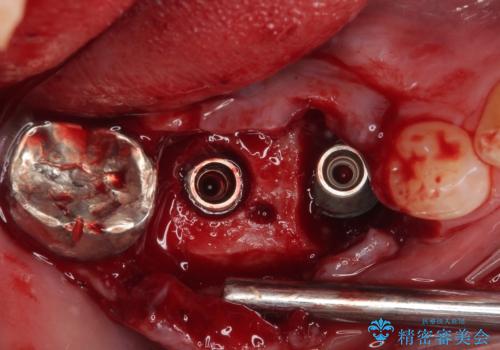

抜歯即時埋入部と後方の欠損部は、即日荷重(インプラント埋入と同時に仮歯を装着すること)が可能な安定値が得られましたが、長い期間欠損した状態で過ごすと、欠損部に舌を押し当てる癖が発現してしまい、舌からの側方圧でインプラントが脱離するリスクが著しく高まってしまうため、即日荷重は行いませんでした。

おかげでインプラントは無事に生着し、僅か4ヶ月で治療を終えることができました。